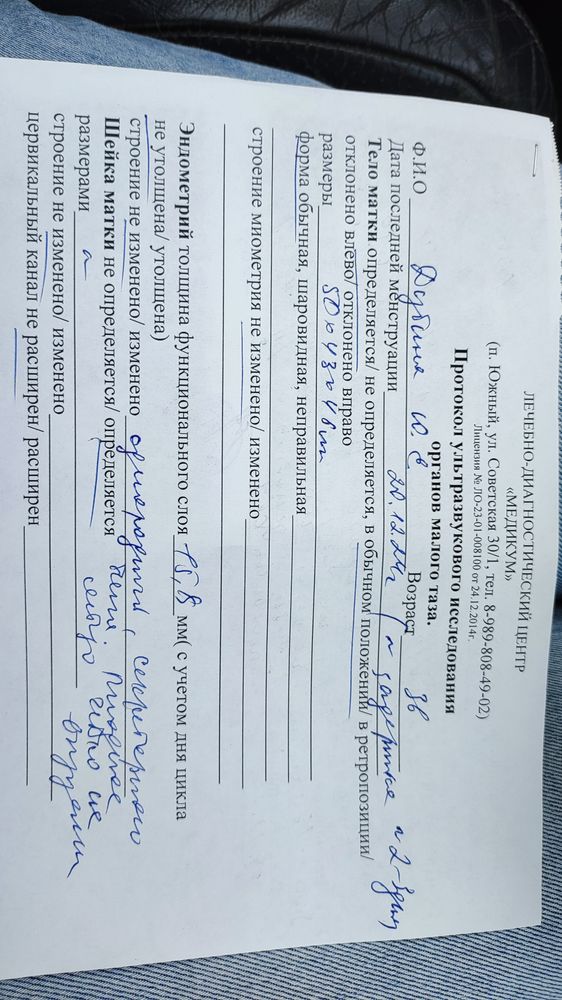

Сходила я сегодня на УЗИ. Лучше бы не ходила. В матке ничего нет. По последним М пять недель. Но факту гораздо меньше. Узистка говорит, что была поздняя овуляция. Числа 9 ПА был 7. Первая бледная полоска была 16 января. И скорее всего это был день прикрепления. Эндометрий хороший, ЖТ в левом яичнике. Я уже перепугалась за бхб. Купила эвик домой, а там почти сравнялись полосочки.